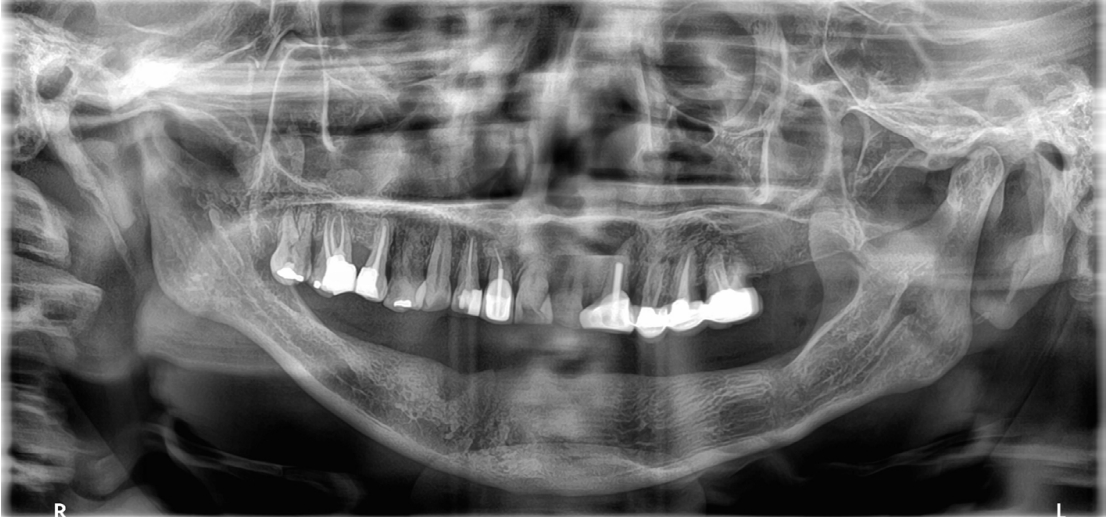

Fig. 2.

Denture wear is detected in posterior area of old denture. RPD is converted into complete denture after extraction of both canine.